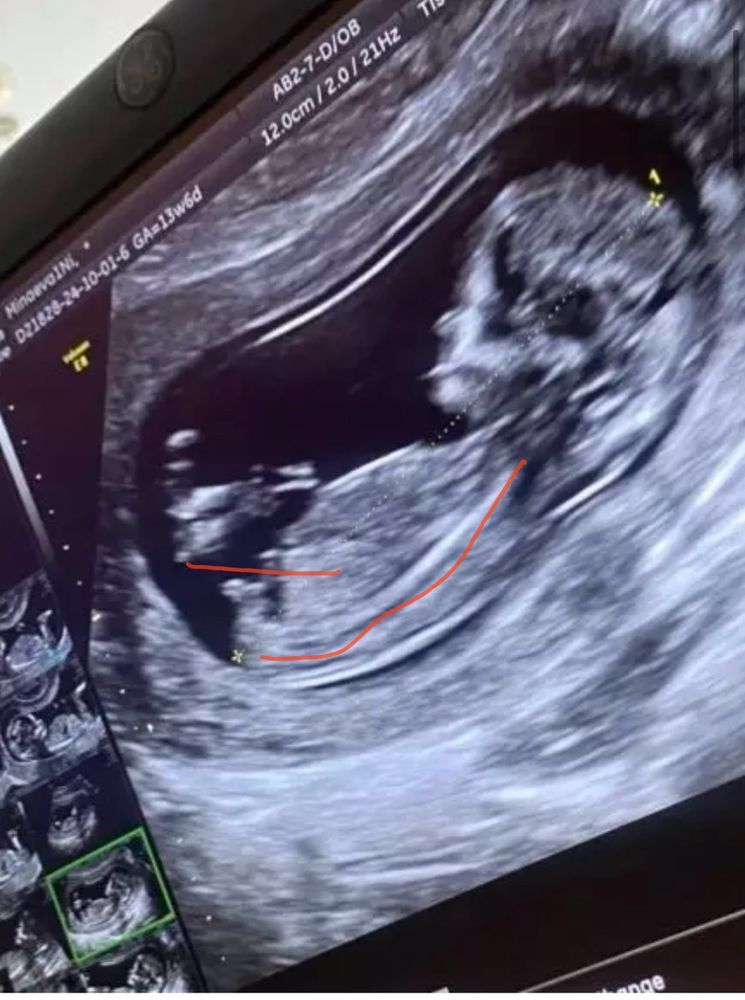

Мальчик. Красным обвела снизу спинку и красным подчеркнула половой бугорок. Видите эту белую линию? Вот эта линия перпендикулярна спинке. У вас мальчик)